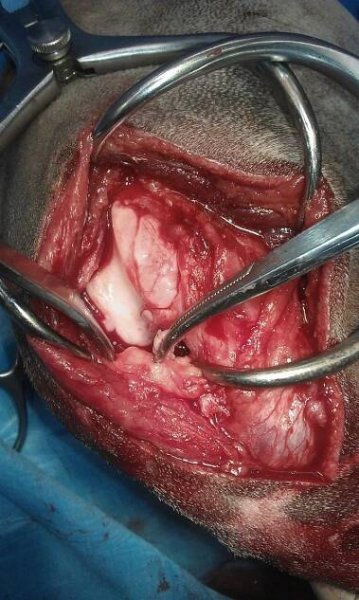

Varikokéla operace- Podvaz rozšířené žíly

operacevarikokely.cz